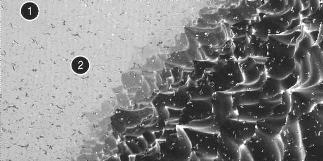

Поверхность OSSEOTITE под увеличением 20 000х

Совершенствование поверхности OSSEOTITE при помощи технологии Дискретной Диспозиции Нано-кристаллов (DCD™)

3. В результате на дважды протравленной поверхности OSSEOTITE происходит дискретная диспозиция кристаллов размером 20-100 нанометров с чрезвычайно высокой силой сцепления.